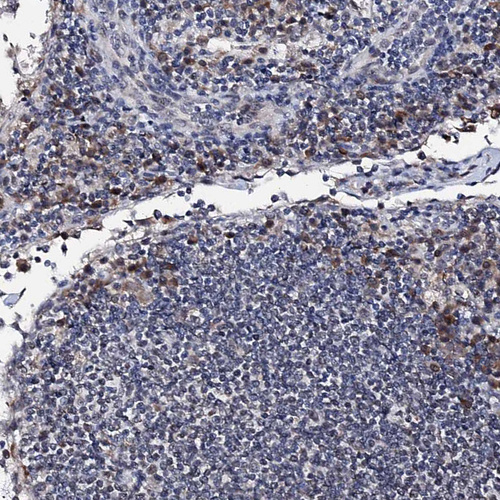

Immunohistochemical staining of human placenta shows strong cytoplasmic and nuclear positivity in trophoblastic cells.